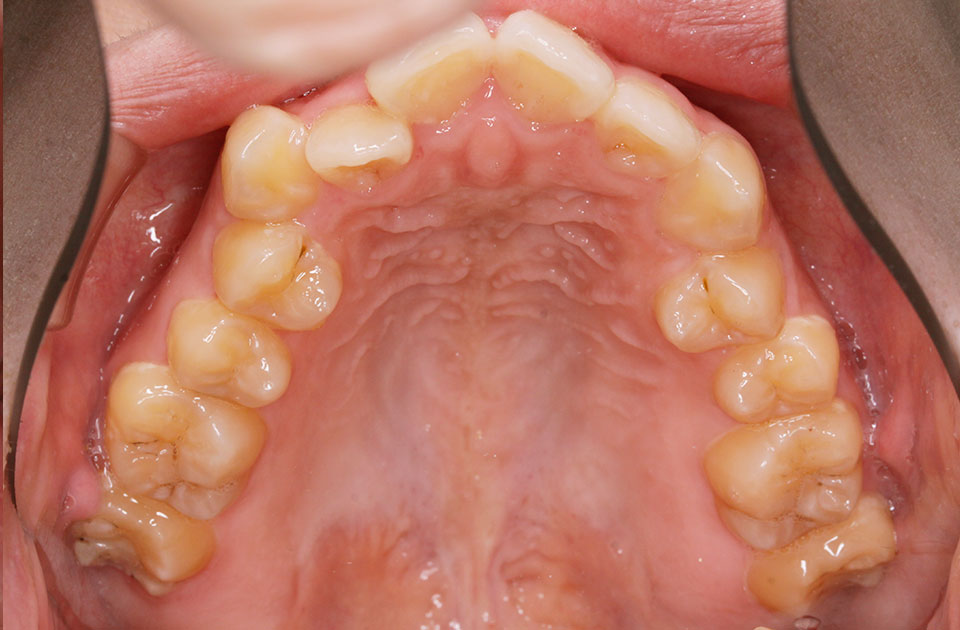

矯正前 上顎

主訴 前突感、口が閉じずらく前歯で物が咬めない。

年齢 20代

治療法 上下顎マルチブラケット装置

抜歯の有無 上顎左右側第一小臼歯、下顎左右側第一小臼歯

治療期間 1年10ヶ月